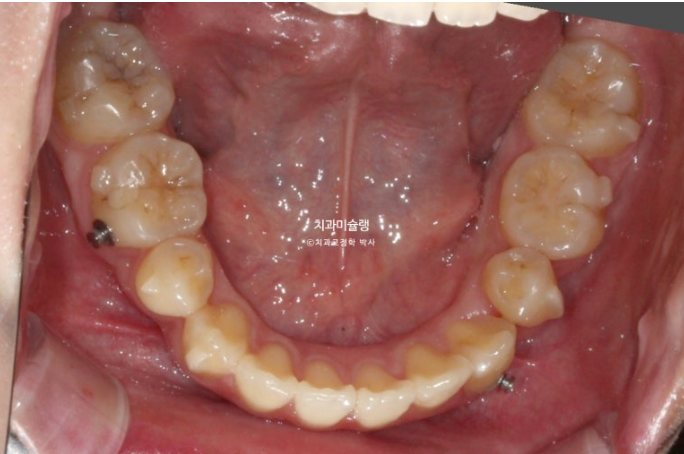

어금니 쓰러짐을 방지하고자 나사도 심고 고무줄도 걸었습니다.

그러나 치료도중 개인사로 인해 15시간밖에 못 끼던 시기가 있어서 이때 일부 어금니가 쓰러졌습니다.

어금니가 쓰러지면 장치가 일부 치아에서 뜨게 되는 현상이 나타납니다.

24.12

중심선은 잘 맞지만 앞니 높낮이 단차가 있습니다.

어금니 교합이 약간 뜹니다.

덧니 배열은 대부분 완성되었으나

엑스레이에서 보이듯 이미 쓰러진 일부 어금니들을 세우고

미세하게 남은 발치공간을 닫고 교합을 안정화 시키고자 재제작에 들어갑니다.